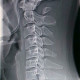

Mohon konsul pasien usia 30 tahun dengan keluhan nyeri leher dan area bahu sudah 3minggu. Keluhan nyeri lebih nyaman kalau pasien mengangkat lengan keatas.

Pasien sendiri tidak ada riwayat trauma

Hasil rontgen cervical pasien seperti demikian